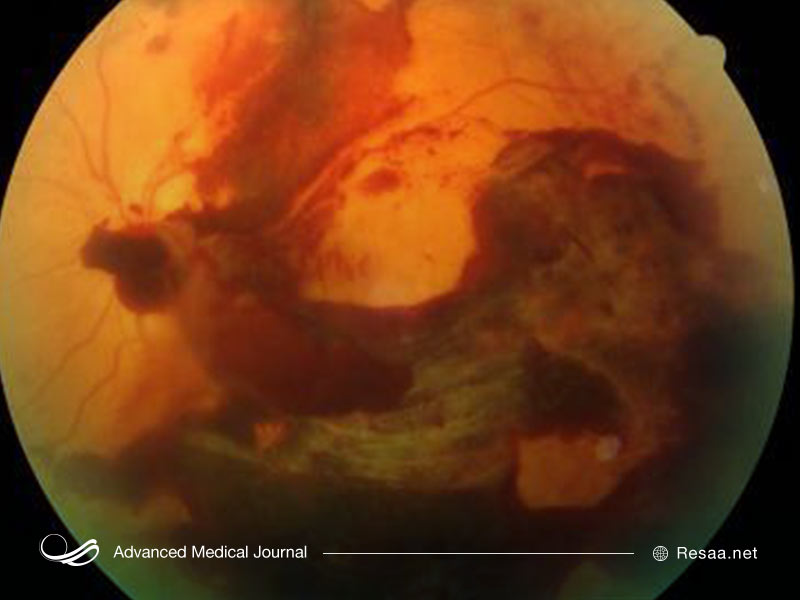

- خونریزی زجاجیه: رگ های خونی تشکیل شده، خونریزی می کنند و به این ناحیه می ریزند. در صورتی که خونریزی اندک باشد، ممکن است بیمار در میدان بینایی خود تنها چند نقطه سیاه شناور ببیند. در موارد شدیدتر، خون می تواند این فضا را پر کند و بینایی بیمار را کاملاً مسدود کند. خونریزی زجاجیه به خودی خود باعث از بین رفتن دائمی بینایی نمی شود. خون اغلب در طی چند هفته یا چند ماه از چشم پاک می شود. اگر شبکیه بیمار آسیب نبیند، ممکن است بینایی به وضوح قبلی خود بازگردد.

![خونریزی زجاجیه در بیماری رتینوپاتی دیابتی]()

- جداشدگی شبکیه: رگ های خونی غیرطبیعی مرتبط با رتینوپاتی دیابتی، رشد نوعی بافت پیوندی به نام بافت اسکار را تحریک می کنند که می تواند شبکیه را از دیواره چشم جدا کند. این عارضه منجر به ظهور لکه های شناور، جرقه هایی از نور در میدان بینایی بیمار و کاهش شدید بینایی می شود.